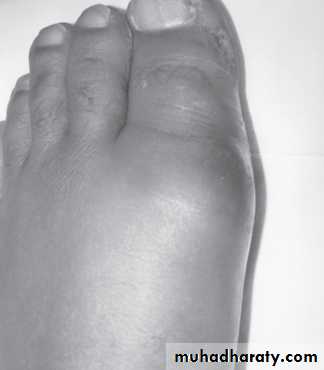

The first clinical symptom of gout is usually an acute, self-limited, monoarticular inflammatory arthritis affecting the joints of the lower extremities. Gout has a predilection for the first metatarsophalangeal joint(Podagra). As many as 50–70 per cent of first gout attacks occur in the big toe. Other frequently involved joints include those of the foot, ankle, knee, wrist, elbow, and the small joints of the hands. The large axial joints and those of the spine are uncommon sites for early acute gout attacks.

The onset of an attack occurs suddenly and often late at night or early in the morning. Patients will describe very severe pain, associated with swelling, extreme tenderness, and redness overlying the joint. Without intervention, the attack will usually subside within 5–7 days.

Physical examination shows signs of inflammation with erythema, warmth, and swelling over the joint, often extending to the overlying skin. There is exquisite tenderness over the affected joint.